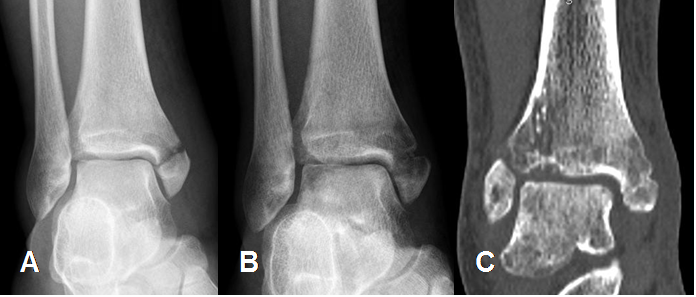

Fig 44. Osteoporosis regional.

A: Rx AP. Fractura del maléolo interno.

B: Rx AP y C: TAC reconstrucción coronal 4 meses después. Signos de osteopenia sobre el tobillo, con incompleta consolidación de la fractura.